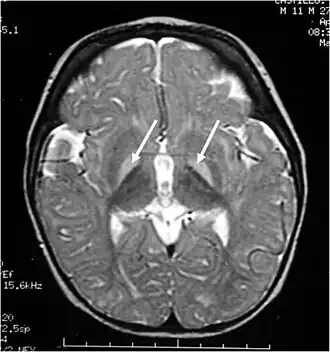

![]() Resonancia magnética de la cabeza. Lesiones hiperintensas de los ganglios basales en T2, marcadas con una flecha blanca. | ||

- Los ganglios basales (sobre todo en el globo pálido, el putamen y el núcleo caudado).